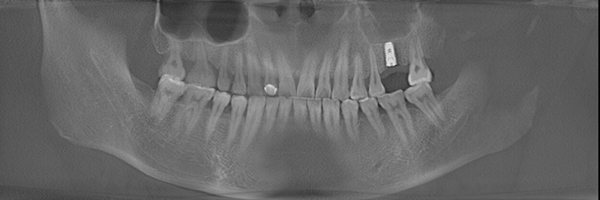

种牙成功后的郑先生口腔ct全景